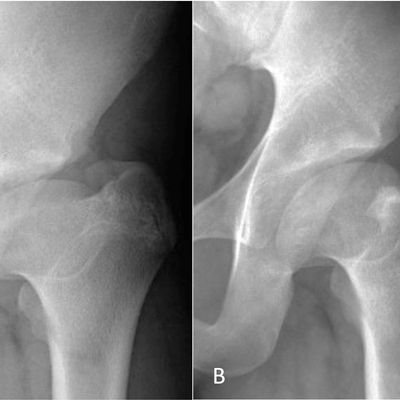

Click on an image below to view more info.